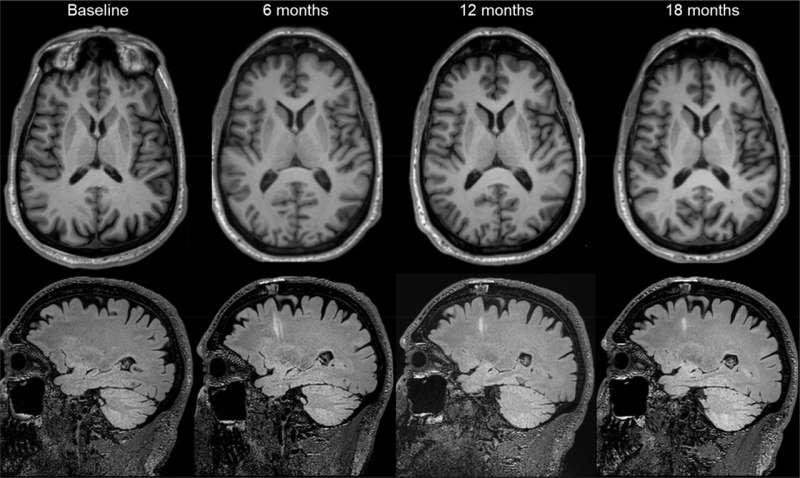

第二項試驗在美國和加拿大各地進行,Viviane Tabar及其同事探究了源自人類胚胎干細胞的多巴胺能神經元祖細胞產品(bemdaneprocel)的安全性。12名患者(平均年齡67歲)接受了手術,將bemdaneprocel移植到大腦兩側的殼核。5名參與者接受了低劑量(每核0.9百萬個細胞),7名參與者接受了高劑量(每核2.7百萬個細胞)。

該細胞產品總體耐受性良好,在18個月的隨訪期內未報告與治療相關的嚴重不良事件。此外,未出現此前用于治療帕金森病的胎兒組織移植相關運動障礙的發生。

此外,低劑量組和高劑量組患者的運動功能均有所改善(這是該研究的次要結果)。然而,不同測量參數的改善程度存在差異。